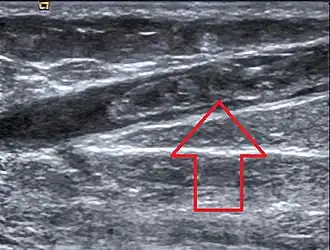

Image échographique montrant une thrombose de la grande veine saphène

Le diagnostic repose généralement sur l'échographie lorsque la veine est accessible par cet examen[1].